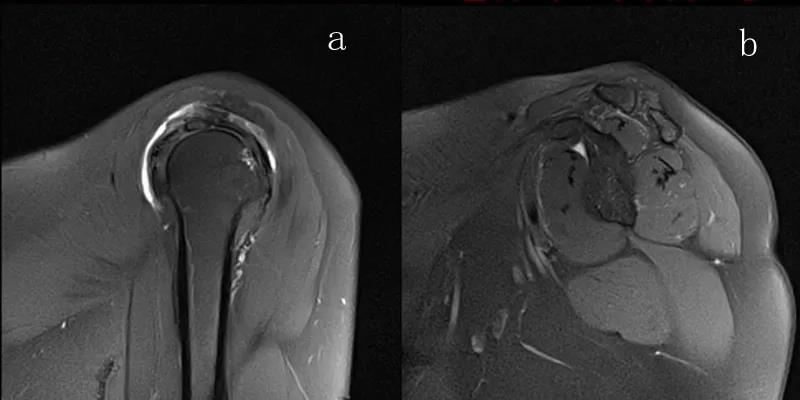

图21 斜冠状位(临床常用)a.T2,b.T1

图22 斜矢状位 a.冈上肌出口,肩袖诊断不如斜冠状位;b.冈上肌及肌腹脂肪浸润成度,评估手术与否

图23 横断位a.正常肩胛下肌;b.肩胛下肌损伤